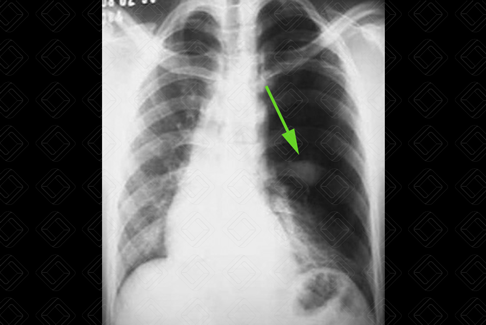

Texto alternativo para a imagem Figura 3. Créditos: Dra. Elazir Mota - Rio de Janeiro/RJ

Descrição da figura 3: Hipertransparência no pulmão esquerdo com discreto desvio do mediastino contralateralmente. Há pequena mucocele no hilo pulmonar esquerdo (seta verde), compatível com atresia brônquica.

• Causas pulmonares: Congênitas: enfisema lobar congênito ou hiperinsuflação pulmonar congênita (figura 2), atresia brônquica (figura 3), malformação pulmonar congênita (MAC); adquiridas: síndrome de Swyer James, causas de obstrução brônquica parcial do brônquio (aspiração de corpo estranho, plug mucoso, tumor endobrônquico), tromboembolismo pulmonar maciço, pneumectomia;